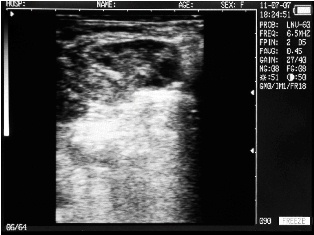

Endometritis in the uterus of the cow